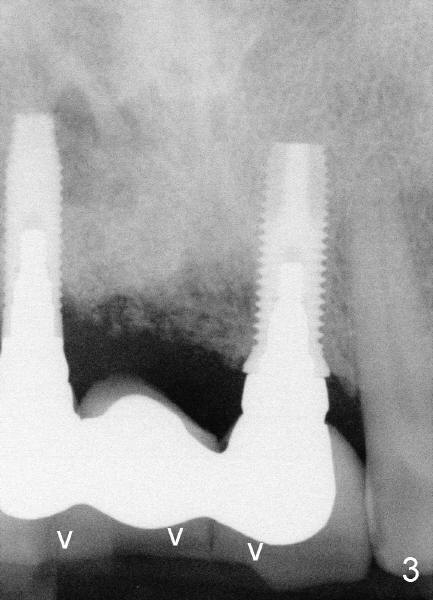

Fig.1 was taken when the new bridge was temporarily cemented (mirror view, Jan. 28, 2010). Arrowheads indicate enamel chip from the lingual cusps of the upper 2nd premolars. On Nov. 11, 2010, the bridge became loose again and was cemented permanently. Two months later (Jan. 27, 2011), porcelain chipped again as shown in Fig.2 and 3 (white arrowheads; black arrowhead points to wear facet of the tooth #6). The chipped bridge was removed.